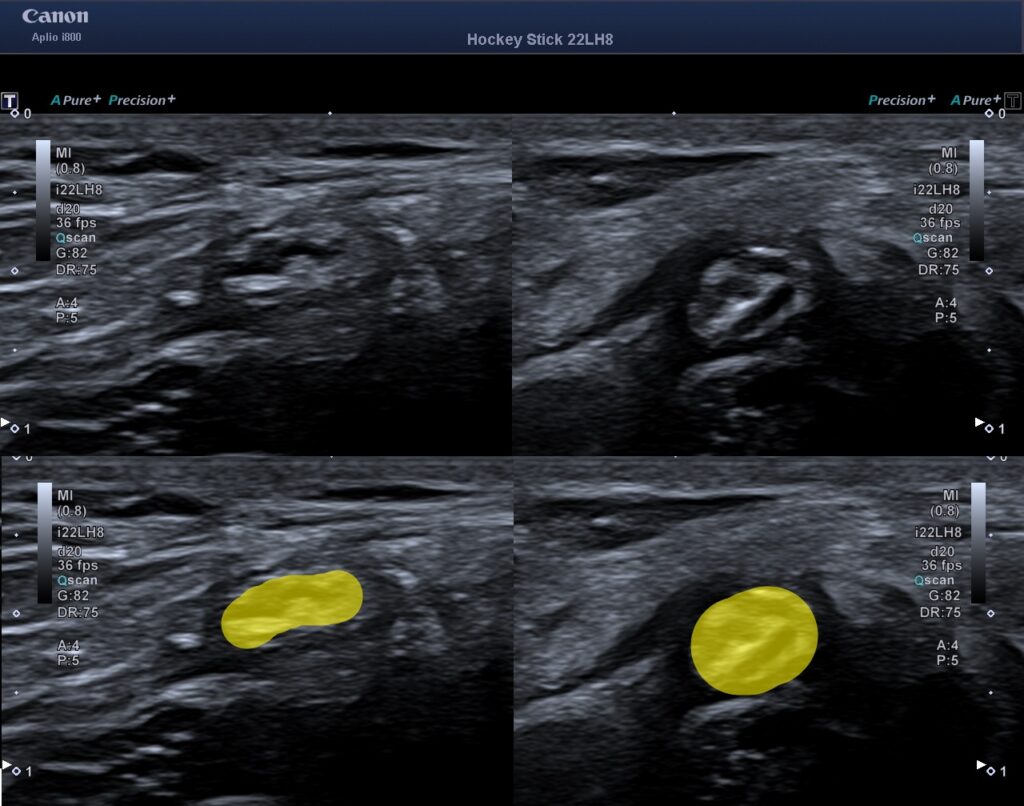

City-Kliniken i Göteborg erbjuder ultraljudsdiagnostik och kan med hjälp av detta se om nerven är påverkad.